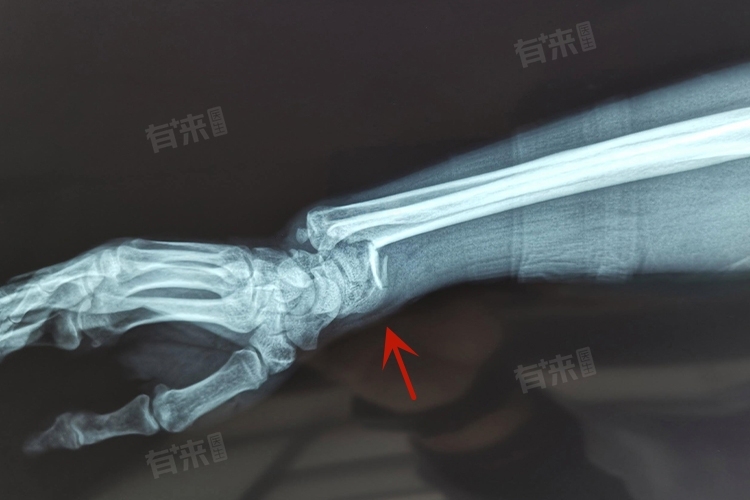

4、诊断方法:餐叉样畸形的诊断主要依据患者的病史、临床表现及影像学检查。X线片是首选检查手段,可清晰显示骨折的部位、类型及移位情况。对于怀疑伴有神经血管损伤的患者,可能还需进行MRI或CT扫描以进一步评估。